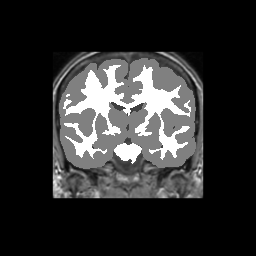

Accuracy is reported as Dice overlaps between a tool's segmentation and the Internet Brain Segmentation Repository (IBSR) manual segmentation for each of the 18 IBSR subjects. The inter-tool comparison (on the left below) shows the median Dice coefficient for each tissue class. The overlaps for FSL (from which the median values are drawn) are shown in the plot on the right.

Subject Accuracy (IBSR)

Overlap coefficients for each tissue class are shown here for each IBSR subject. Select a subject below to see the FSL results compared to other tools.

Test/Retest Reliability

FSL was run on each scan in the Brain Segmentation Testing Protocol (BSTP) between-scanner test/retest dataset. Select a subject below to see volumes for each subject across the subject's scans.